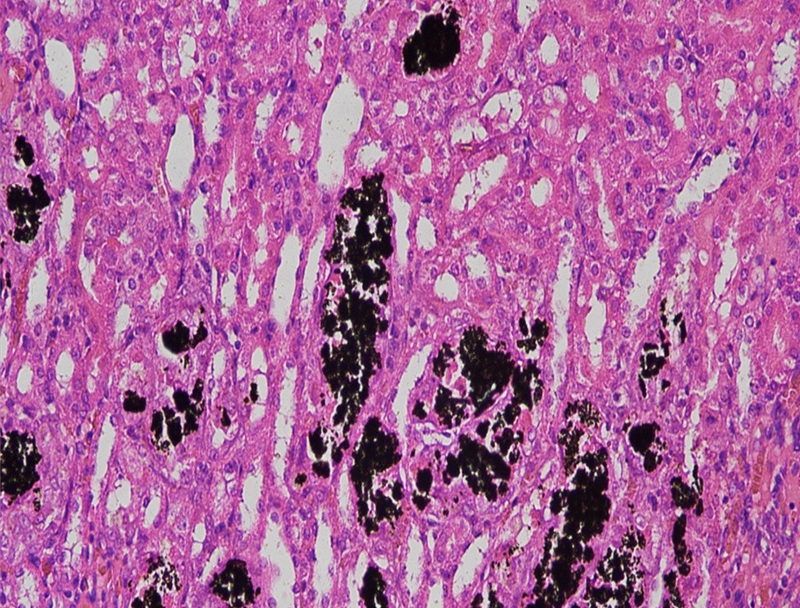

以下是關于 Von Kossa 染色的詳細介紹:基本信息定義:Von Kossa 染色是一種特殊的組織學染色技術,用于檢測組織和樣本中的鈣鹽沉積,尤其是磷酸鈣染色原理:利用銀離子與組織中的磷酸鈣鹽或碳酸鈣鹽發生反應,在酸性···